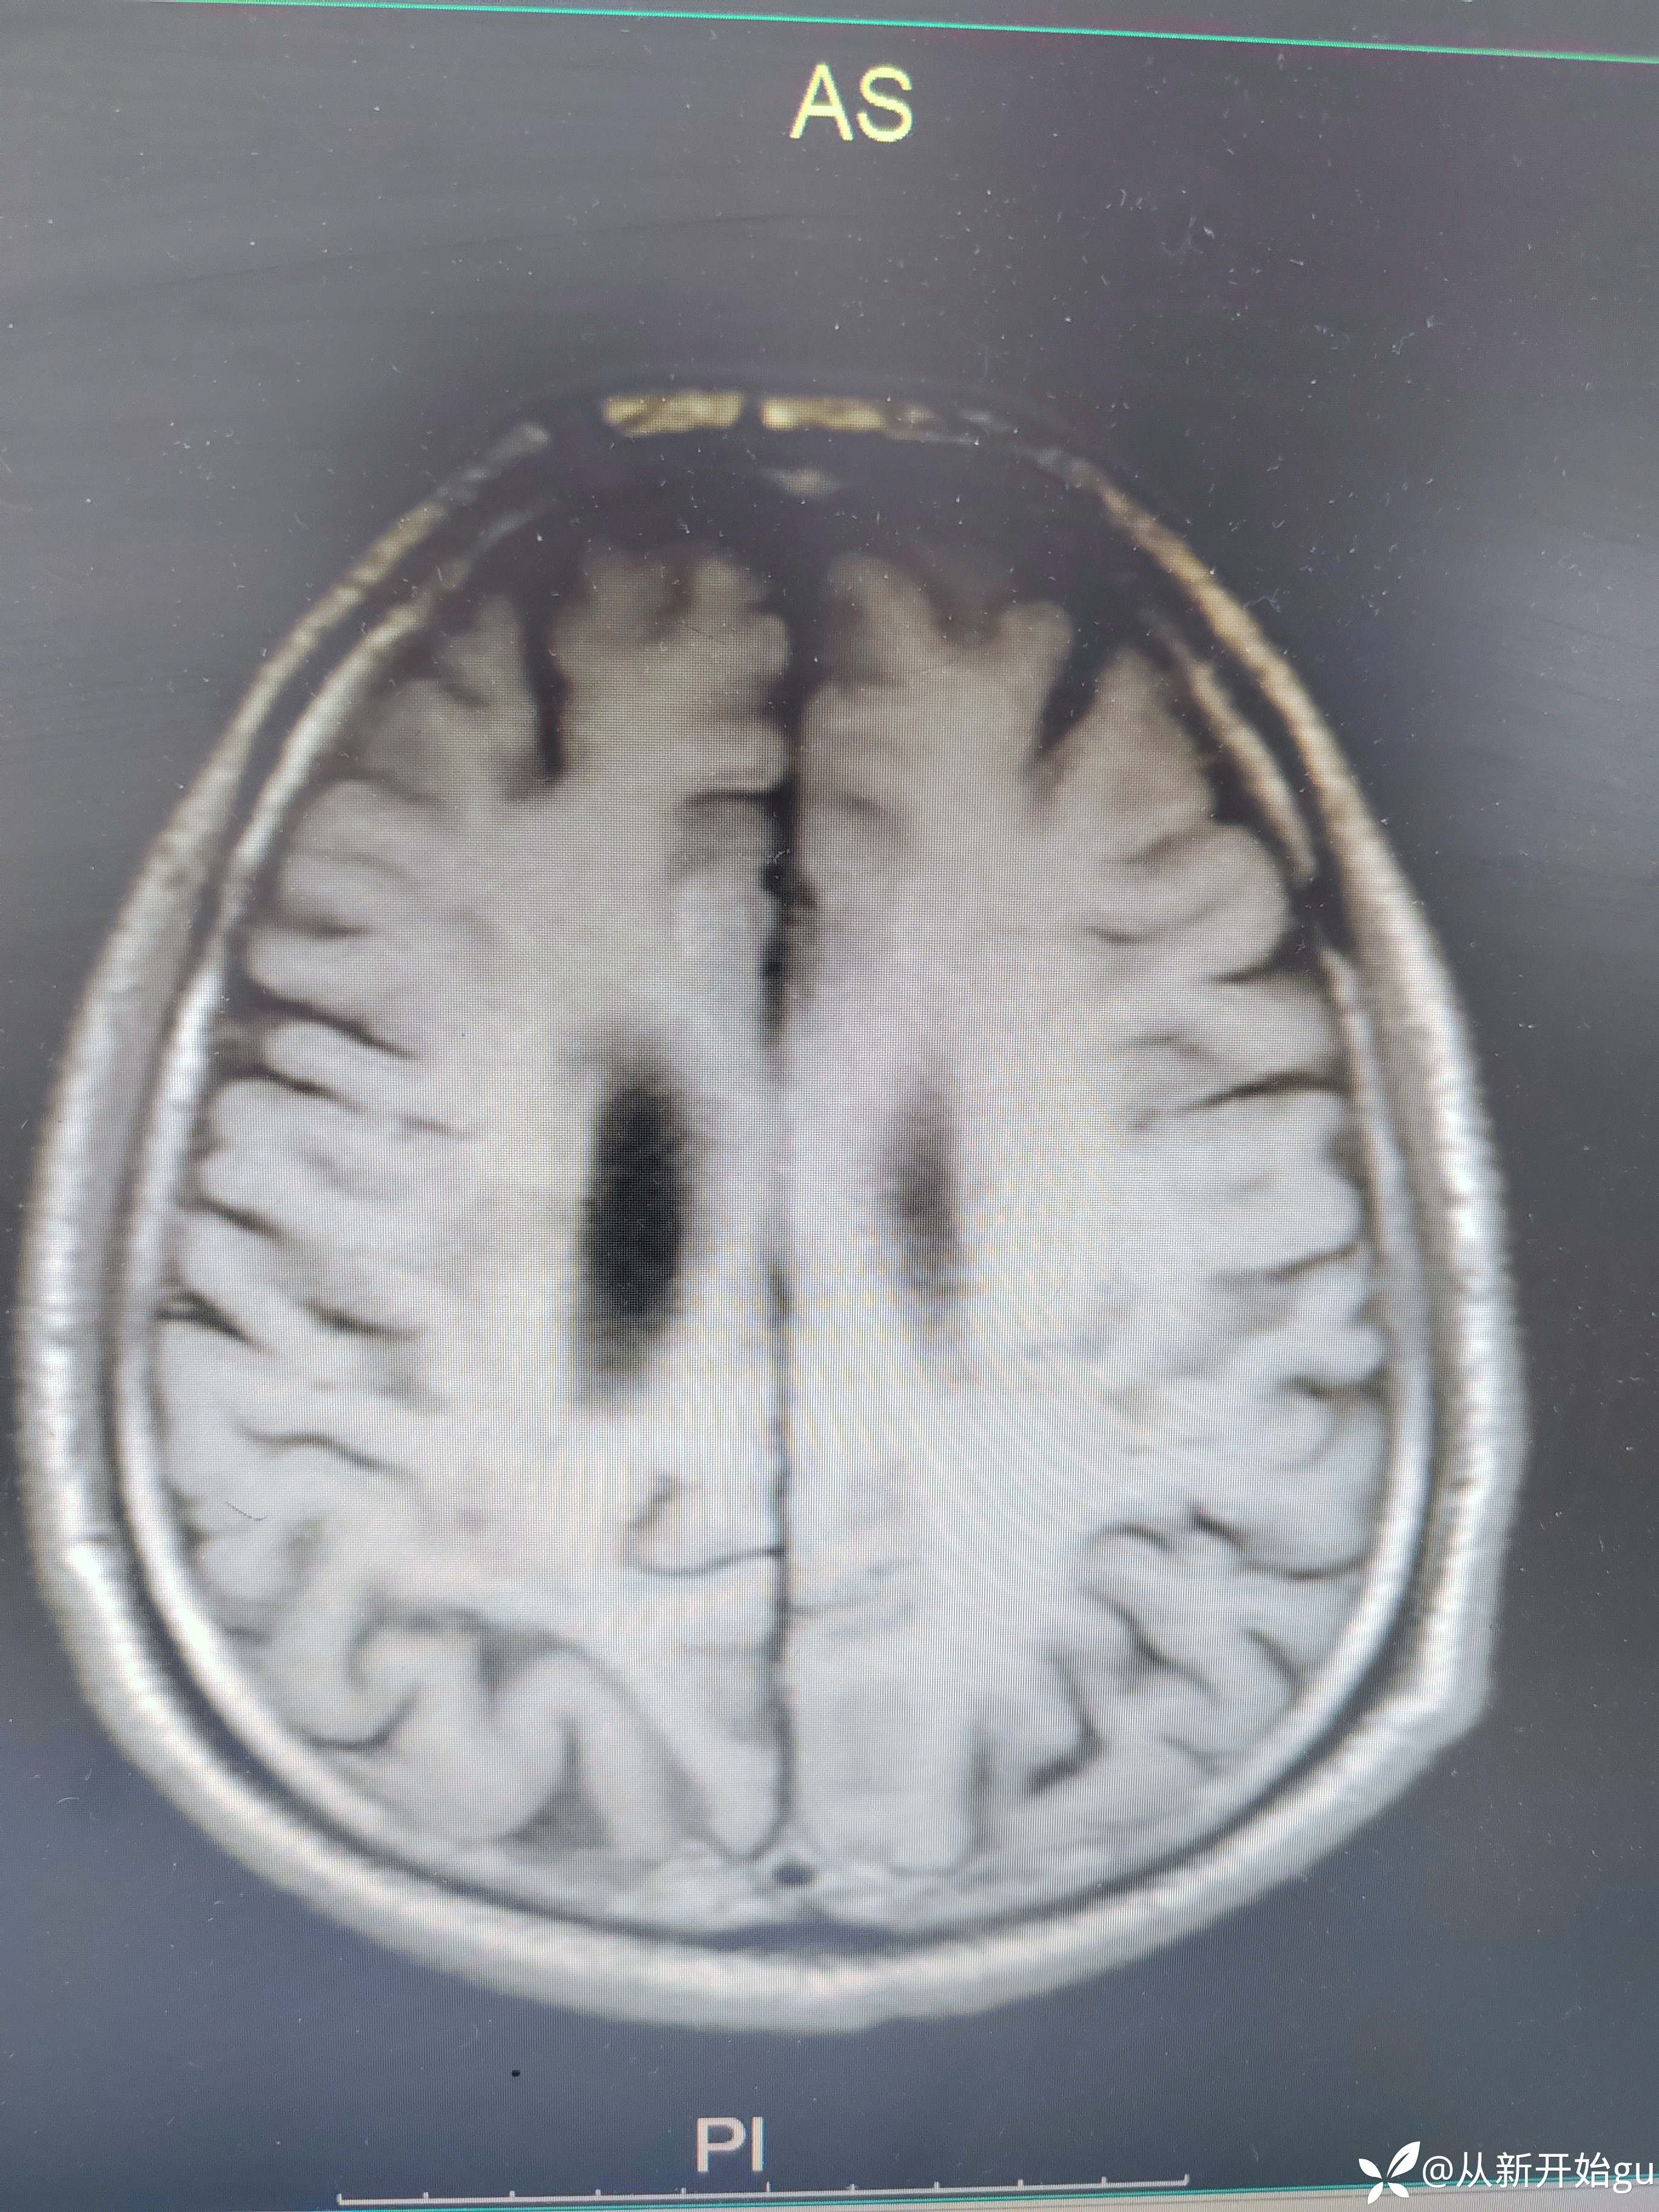

患者男性53岁,主因被发现左下肢活动障碍2.5小时来院,(患者下夜班,于上午9点休息,下午3点醒后出现症状)。既往脑梗死病史9个月,遗留言语不利及口角歪斜的症状。查体:右侧鼻唇沟稍浅,神舌右偏,左侧下肢肌力4级,左侧指鼻试验欠稳准,左侧巴氏征阳性。外院完善颅脑CT无出血改变。来院后完善核磁检查如图所示。